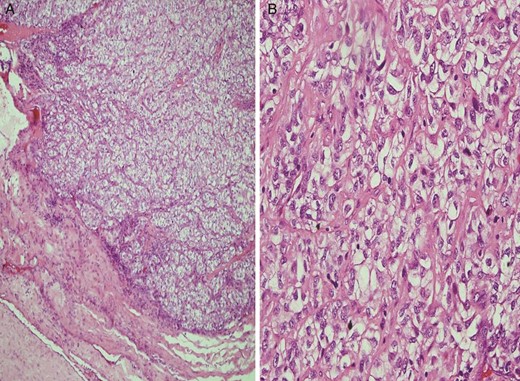

![(A) Histopathologic appearance of the RCC metastasis in the right gluteus maximus muscle (hematoxylin-eosin [H&E] staining, original magnification ×100) and (B) histochemical assay result of the fine-needle biopsy of the mass positive for RCC (RCC ×200).](https://oupdevcdn.silverchair-staging.com/oup/backfile/Content_public/Journal/jscr/2014/10/10.1093_jscr_rju101/2/m_rju10102.jpeg?Expires=1770309259&Signature=YO2YnBHWhio4Y~saVn~SNDYnzkyf~DKvSAwuvuEENpbLf51m8jLDIPBNIudoaDtNySbvDOJ~MIpAr9nMPCHnz9EUplvFzgEN8VmdRK2n62pw3HT8KsZ0lo0D41PRI4~5x2kyWemDSo8DDW7H8SwxuixR24GDL0oluKpunQ8UOts3aQHch2zteO9Yy5oe9z-2Nm95Cfqi2w~GOyab72rWDNIv8xrQYGshULwqW6NzC~kR9sk3pdw4KgXzGY6j5Fq3fP9dXgONohnS17dbIpYtnT04jS3BHI8VhctQ7JOYsvINF2PiyMpdCaqLctxrS~leHZ~ap9UO1k6taobBITZiKA__&Key-Pair-Id=APKAIYYTVHKX7JZB5EAA)

(A) Histopathologic appearance of the RCC metastasis in the right gluteus maximus muscle (hematoxylin-eosin [H&E] staining, original magnification ×100) and (B) histochemical assay result of the fine-needle biopsy of the mass positive for RCC (RCC ×200).